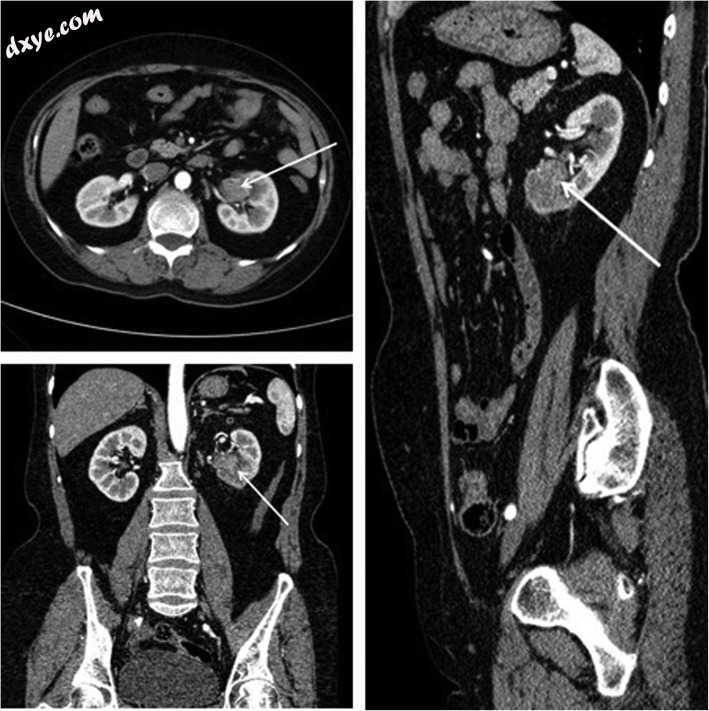

试验组共45例,其中男性24例,女性21例,左侧肿瘤19例,右侧肿瘤26例,肾盂癌31例,输尿管癌14例。对照组共44例,其中男性23例,女性21例。 21名患者的肿瘤位置在左侧,而23名患者在右侧。肾盂癌患者29例,输尿管癌患者15例。所有患者在手术前均行计算机断层尿路造影(CTU)或磁共振尿路造影(MRU)以确定肿瘤位置(图1)。进行肾动态成像和肾小球滤过率(GFR)测试以评估对侧肾功能。进行胸部和腹部CT以排除肿瘤转移,评估心肺功能以排除手术禁忌症。视觉模拟评分(VAS)用于评估术后1小时,12小时,24小时和48小时的疼痛程度。两组患者的一般情况无统计学差异,如年龄,性别,肿瘤部位,肿瘤分期和分级(P> 0.05,表见11)。

图1

通过CT确定肿瘤位置。 箭头表示上尿路尿路上皮癌